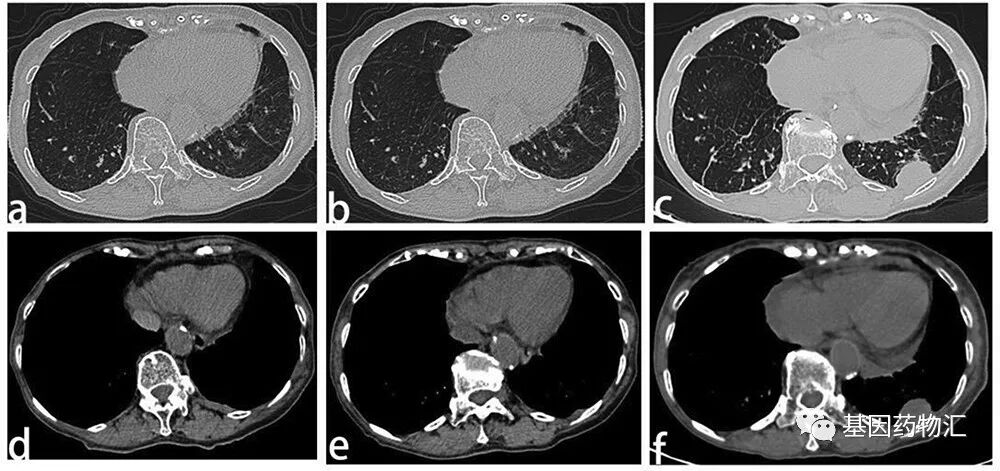

案例三:90岁,12个月

第三个案例来自一位年龄非常大的患者。这位患者是一名90岁的女性,从未吸烟,诊断为左肺腺癌,确诊时有胸腔积液。

患者一线接受了全身性化疗,但是没能取得缓解。由于胸腔积液严重,患者接受了胸腔穿刺术,以及胸腔内滴注顺铂治疗,但很快胸腔积液再次增加,且伴随严重的副作用,呼吸困难。

免疫组化提示患者ROS1为阳性,因此接受了克唑替尼治疗。治疗第1个月,患者的症状出现了明显的改善;治疗仅2个月,患者的呼吸困难症状消失了。此时的影像学检查结果显示,患者的疾病控制稳定。

此后患者又继续接受了10个月的克唑替尼治疗,直至再次复发。从患者确诊到最终因肝肾功能严重不全而死亡,生存期共14个月。